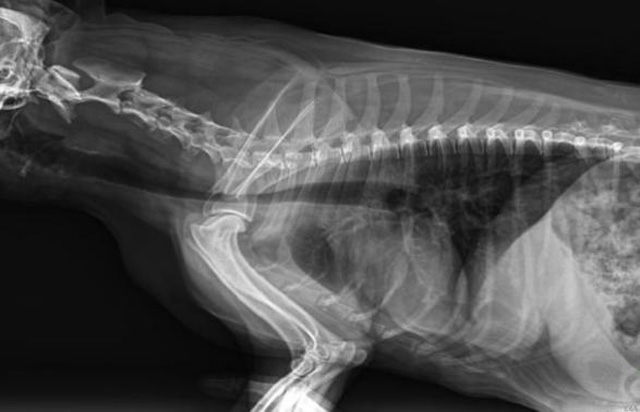

從臨床角度出發(fā),大力發(fā)展動(dòng)態(tài)DR,以精準(zhǔn)的診斷為小動(dòng)物保駕護(hù)航。寵物DR升級(jí)使用雙焦點(diǎn)球管,大尺寸平板探測器,超高頻逆變高壓發(fā)生器。醫(yī)用纖維板臺(tái)面,防止寵物劃傷。寵物DR整機(jī)小巧實(shí)用,骨略結(jié)構(gòu)和器官位置,分類詳細(xì),運(yùn)算更快,讓拍攝條件更科學(xué),有助于提高診斷的準(zhǔn)確性和效率。安裝移動(dòng)非常方便。低輸入電流設(shè)計(jì),220伏常規(guī)電壓。多品種動(dòng)物程序設(shè)定,滿足各個(gè)臨床需求。成像效果顯著,寵物不能言語表達(dá),導(dǎo)致誤診率居高不下。寵物診療均以經(jīng)驗(yàn)診斷為主的方式,確保最小化輻射降低對(duì)醫(yī)生及動(dòng)物的影響。以滿足精細(xì)化的寵物醫(yī)療需求,成為診斷寵物內(nèi)外科疾病的必備工具。使醫(yī)院更有競爭力,為醫(yī)院創(chuàng)收增光添彩。

寵物DR的操作流程是什么呢?第一步首先插上整機(jī)電源,然后按下主機(jī)電源。打開高壓發(fā)生器的電源,工作站主機(jī)電源。等待主機(jī)軟件的自動(dòng)啟動(dòng)。通過軟件登記檢查的寵物信息,選擇寵物檢查拍攝部位。調(diào)節(jié)限速器拍攝區(qū)域。關(guān)閉鉛房門,點(diǎn)擊開始拍攝按鈕。拍攝完成調(diào)整圖像并且輸出。